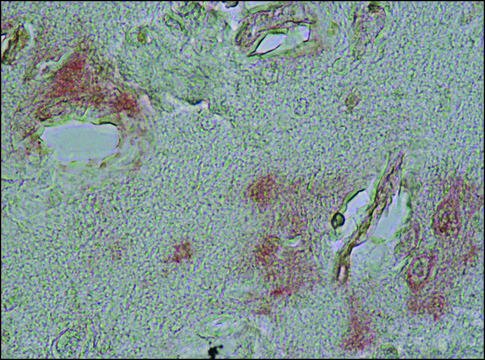

immunohistochemistry (formalin-fixed, paraffin-embedded sections): 1:200 using formic acid treated sections of Alzheimer′s Disease brain

Rabbit polyclonal anti-α-Synuclein antibody is used to tag α-Synuclein for detection and quantitation by immunocytochemical and immunohistochemical (IHC) techniques, such as immunoblotting. It is also used as a probe to determine the presence and roles of α-Synuclein in plaques of Alzheimer′s disease (AD) brains.